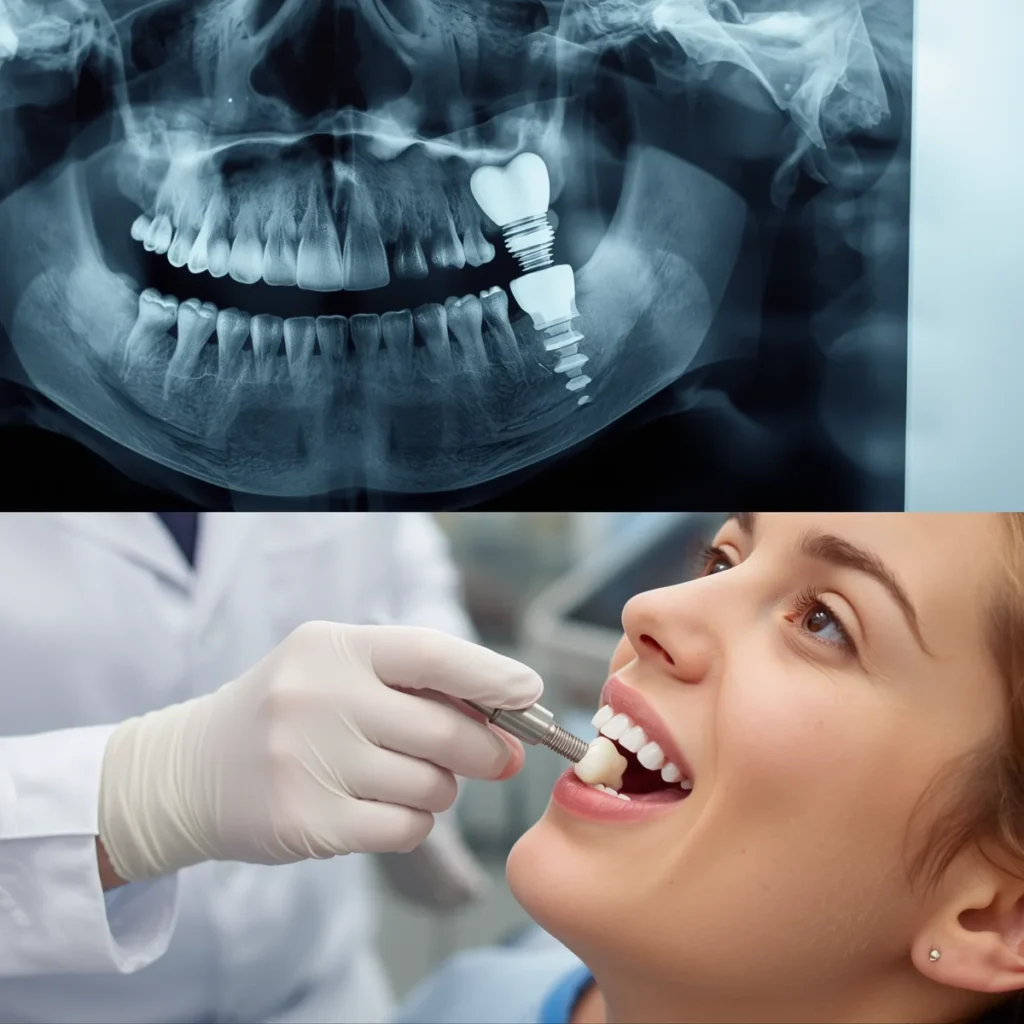

Medically reviewed by Dr. Eugene Bernstein, DDS – Implant Dentist | 24+ Years Experience | Last Updated: March 2026 If a dental implant fails, it can usually be removed and replaced after the area heals. Implant failure is rare, with success rates generally reported between 95% and 98%. Failure is not the end of the […]